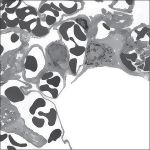

Electron Micrograph of the Lung Containing an Alveolar Macrophage (Dust Cell) at Lower Magnification